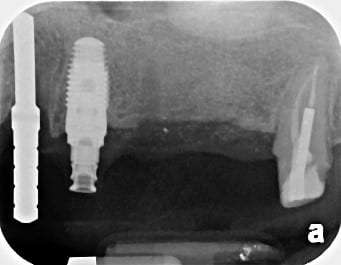

An external sinus lift, where there is very little or no bone to work with, is performed before the actual implant placement and usually covers the floor of the sinus on one side below its protective membrane.

An example of an external sinus lift can be seen below:

Stage 1: No Bone Available to Receive any Implant

Stage 2: Bone Graft Placed in an External Sinus Lift

Stage 3: Implants Placed in the Matured Bone Graft